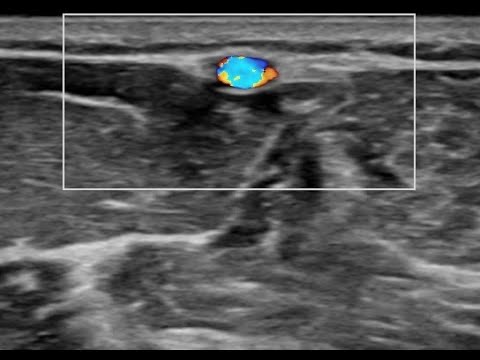

Видео узи артерий

Видео узи артерий 107 фото